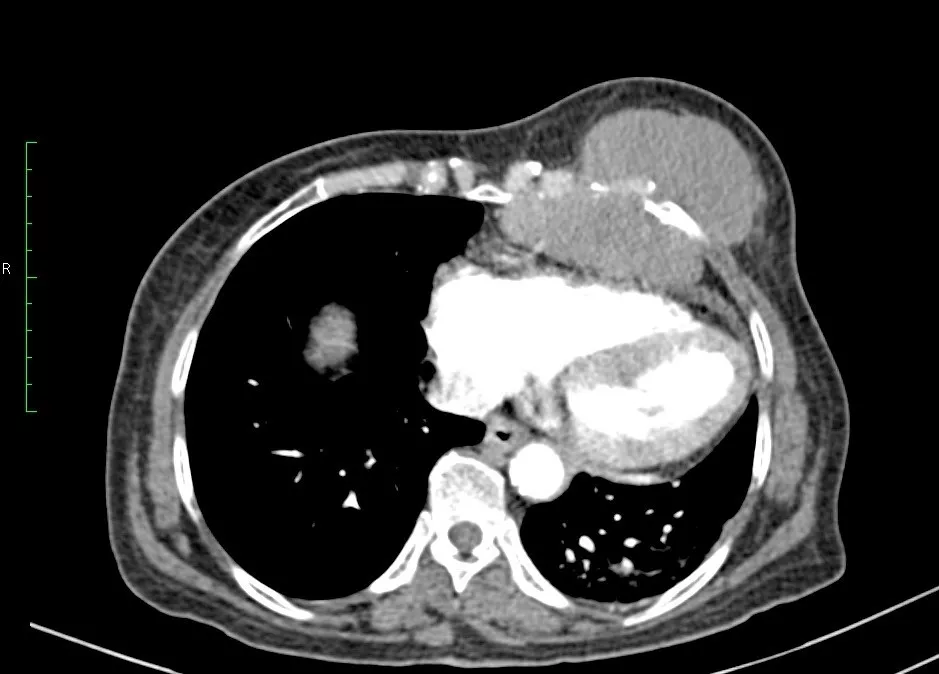

Mammography is an X-Ray examination of breast tissue. The image produced is called mammogram. A mammogram can help detect problems with your breasts, such as cysts or cancer.